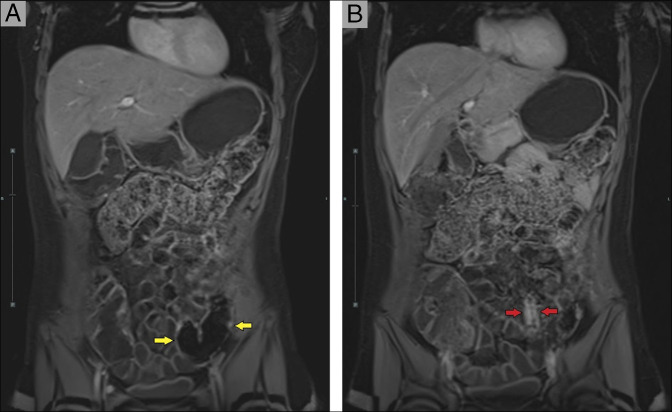

系统性红斑狼疮(SLE)和克罗恩病(CD)共存是罕见的,由于重叠的临床、放射学和组织学特征,给诊断和治疗带来了重大挑战。我们报告了一位24岁的女性,她患有SLE,慢性免疫性血小板减少性紫癜,并新诊断为CD,并接受了批准用于CD的il -23抑制剂risankizumab的治疗。她在12个月内获得了完全的临床和放射学缓解,没有SLE发作。据我们所知,这是首例利桑单抗成功用于SLE和CD患者的病例。需要进一步的研究来评估白介素-23抑制剂对这类治疗不足的患者群体的长期安全性和更广泛的适用性。

The coexistence of systemic lupus erythematosus (SLE) and Crohn disease (CD) is rare and presents significant diagnostic and therapeutic challenges due to overlapping clinical, radiologic, and histologic features. We present a 24-year-old woman with SLE, chronic immune thrombocytopenic purpura, and newly diagnosed CD treated with risankizumab, an interleukin-23 inhibitor approved for CD. She achieved complete clinical and radiologic remission of CD without SLE flares over 12 months. To the best of our knowledge, this represents the first documented case of risankizumab successfully used in a patient with SLE and CD. Further research is needed to assess the long-term safety and wider applicability of interleukin-23 inhibitors for this underserved patient population.